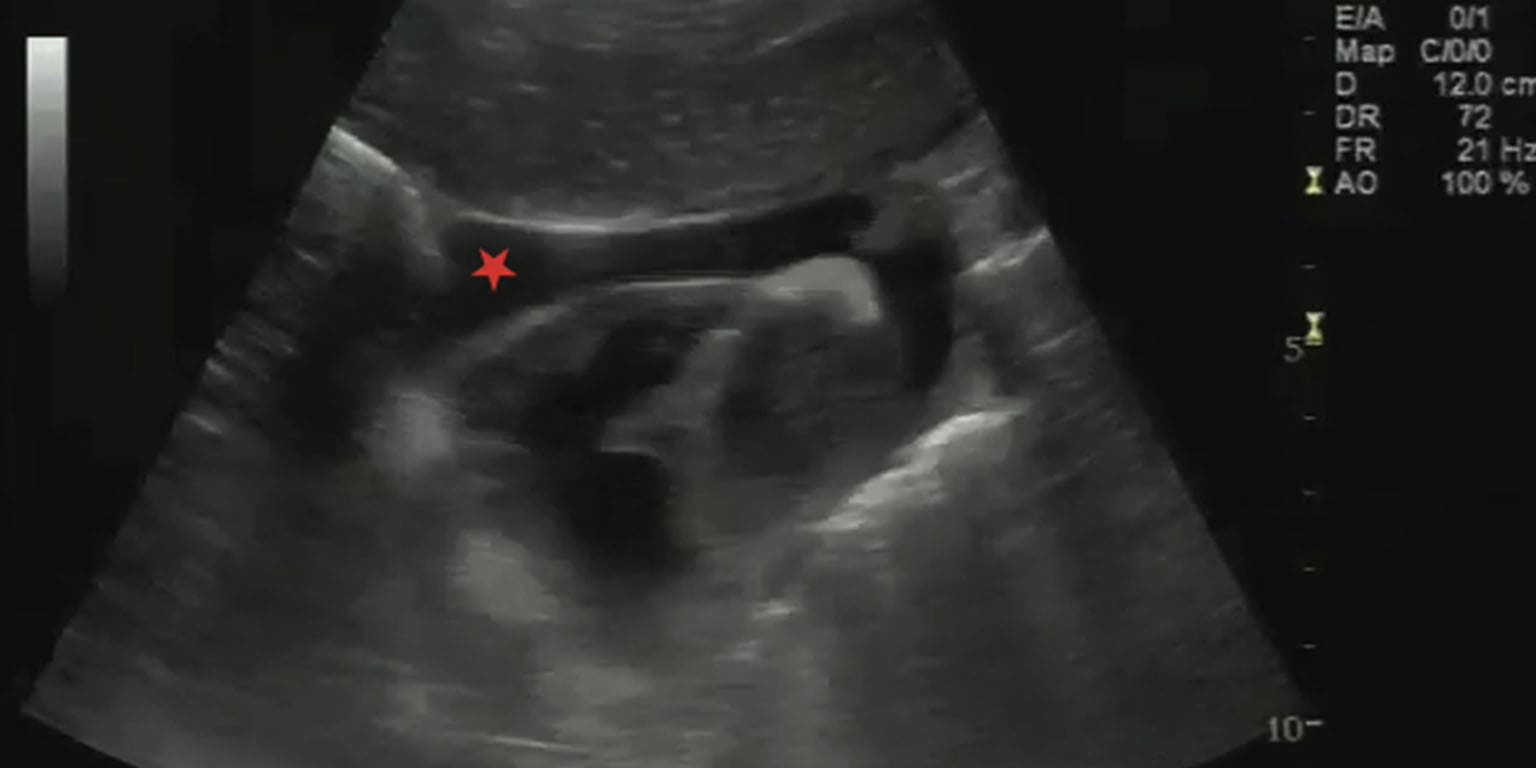

Neonatal Neurosonography

Bedside sonography machine is available. Expert radiologists trained in neonatal neuro-sonogram carry out the sonography as per protocol.